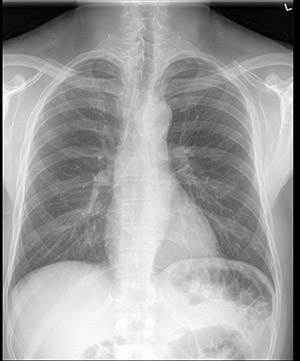

Standard Chest x-ray